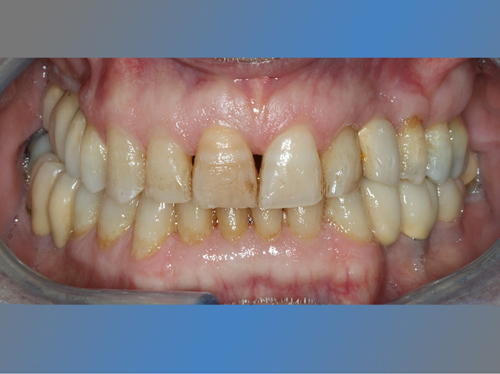

Félix Miquel Sempere acude en 2001 a la clínica dental IDIM tras varios intentos fallidos de colocación de implantes dentales en otra clínica dental.

Después de 17 años los implantes siguen estables y sanos. Félix tiene una sonrisa completa y una boca sana, y nos cuenta que va tan bien que no distingue entre sus dientes naturales y los implantes.